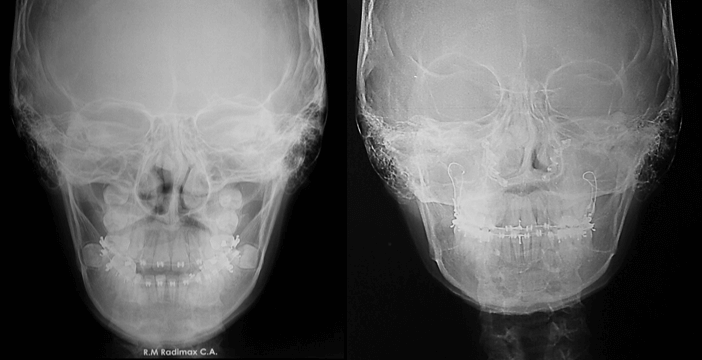

Radiografía Postero Anterior Inicial

Donde se puede evidenciar la marcada asimetría facial e hiperplasia condilar izquierda.

Radiografía Postero Anterior Final

Radiografía Postero Anterior Comparativa